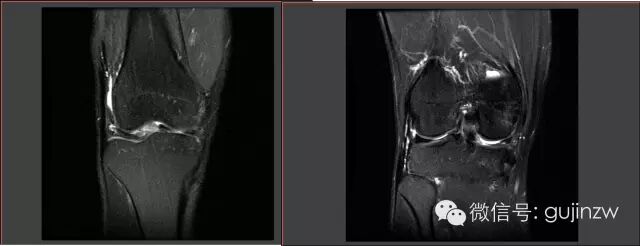

病例3

• 男,25岁。

• 主诉:打篮球扭伤致右膝关节疼痛半年。

• 症状:轻微跛行,右膝关节疼痛,活动时有不稳感,无交锁、打软腿。

• 体征:膝关节活动度:0-135度,浮髌试验弱阴性,内外侧关节间隙无压痛。

• 被动挤压:麦氏征(-),Apley征(-)。

• 主动挤压:Ege‘s征(-),Thessaly  20°征(+)。